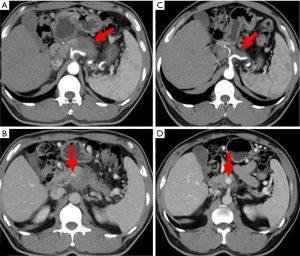

A 45-year-old man presented with a 2-month history of back and abdominal pain, a 4-year history of diabetes mellitus, and a 20-year history of chronic hepatitis B. His serum concentrations of CA19-9 and carcinoembryonic antigen (CEA) were >1,000 and 17.22 U/L, respectively. Other blood values were normal. Enhanced computed tomography (CT) showed that the tumor was located at the neck and body of the pancreas with involvement of the hepatic artery, splenic artery, and superior mesenteric vein (Figure 1). Positron-emission tomography-CT (PET-CT) showed a mass with high metabolic activity in the same region but did not detect a metastatic lesion (Figure 2). Endoscopic ultrasonography-guided biopsy confirmed the diagnosis of pancreatic adenocarcinoma. Four cycles of FOLFIRINOX were administered. During treatment, the patient experienced only grade-2 adverse events (vomiting and nausea). After chemotherapy, we evaluated the enhanced CT data and found that the size of the tumor was obviously smaller (Figure 1). A distal pancreatectomy and splenectomy was performed and histopathology revealed a well-differentiated PDAC with no detectable metastasis in the regional lymph node (0/15), and significant necrosis and fibrosis were present in the tumor (Figure 3). After operation the patient accepted five cycles of FOLFIRINOX treatment and was alive 8 months after surgery with no detectable recurrence.

A 59-year-old man presented with a 1-month history of abdominal distension as well as jaundice of the skin and sclera for 18 days. He had a 10-year history of diabetes mellitus and hypertension. He had abnormally high concentrations of biomarkers of liver tumors and function (CA19-9, 264.1 U/L; CEA, 8.0 U/L; alanine aminotransferase, 144 IU/L total bilirubin, 415 µmol/L; and direct bilirubin, 223 µmol/L). Magnetic resonance cholangiopancreatography (MRCP) revealed bile duct dilatation and a mass at the head of the pancreas. Enhanced CT detected a metastatic lesion in the right lobe of the liver (Figure 4). Endoscopic ultrasonography-guided biopsy confirmed the diagnosis of pancreatic adenocarcinoma. Percutaneous transhepatic cholangio drainage was then performed to reduce jaundice, which was followed by five cycles of FOLFIRINOX. During the second cycle of chemotherapy, a grade-3 adverse event (febrile neutropenia) occurred. Therefore, the remaining three treatment cycles used an 80% dose of FOLFIRINOX. After chemotherapy concluded, enhanced CT revealed obvious reduction of the pancreatic and liver lesions (Figure 4). The patient subsequently underwent pancreaticoduodenectomy, during which intraoperative brightness mode ultrasound did not detect suspicious liver lesions. Histopathology, which revealed a PDAC that exhibited intermediate differentiation, detected two of 31 regional lymph nodes with metastasis. After operation the patient accepted six cycles of FOLFIRINOX treatment and was alive 12 months after diagnosis without detectable recurrence.